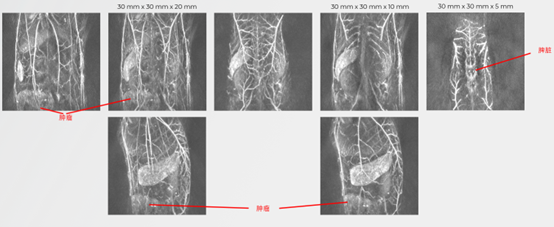

小鼠肿瘤组织监测:

无标记的小鼠肿瘤组织成像

无毛小鼠(左)和 nu/nu 小鼠(右)中的人类乳腺癌异种移植(BT474 细胞)。(a、b)显示了相机观察结果和相应的冠状 MIP 板,由 700 nm 和 1064 nm 激光激发获得的 TriTom 图像构建而成。蓝色箭头和红色 ROI 表示高分辨率图像中可见的浅表血管特征和肿瘤环境。(c)复合皮肤(532 nm;灰色)和深层组织(890 nm;红色)3D 图像。肿瘤大小 = 10.6 x 4.7 x 11.6 mm3